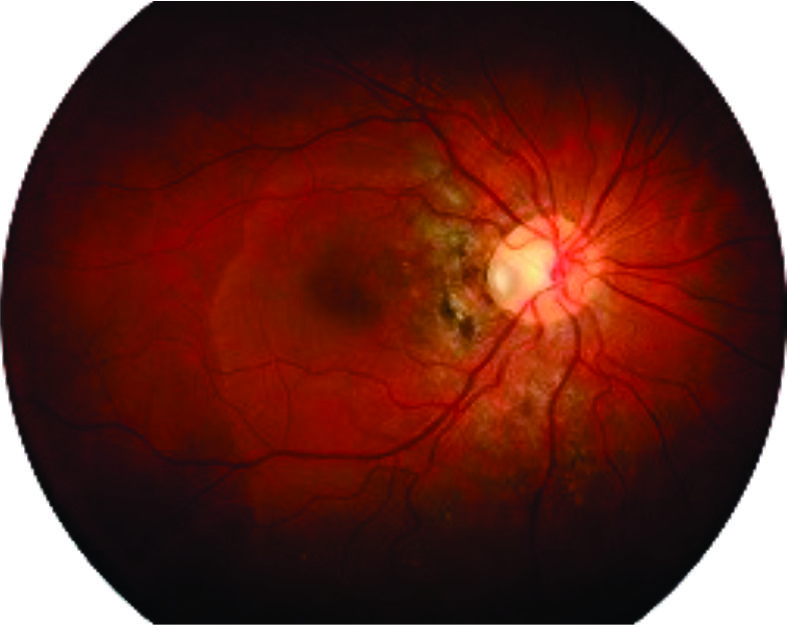

Optic disc pit is a congenital anomaly of the optic nerve frequently associated with macula detachment. It has a poor visual prognosis if left untreated. The treatment of the optic disc remains controversial and includes the use of laser along the edge of the optic nerve, vitrectomy with gas tamponade with or without removal of posterior hyaloid. We report a case of a 19-year-old female with a longstanding macula detachment due to optic disc pit who was treated with vitrectomy with removal of posterior hyaloid, gas tamponade, and laser. Despite longstanding macular detachment the final visual acuity was 20/25.